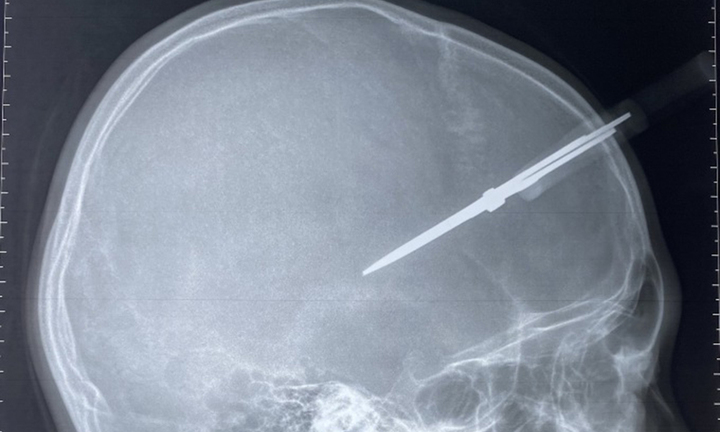

Bệnh viện Đa khoa Đức Giang (Hà Nội) vừa tiếp nhận trường hợp P.T.H (12 tuổi, ở Gia Lâm, Hà Nội) bị kéo thủ công của bạn đâm vào đầu đúng vào buổi học cuối năm.